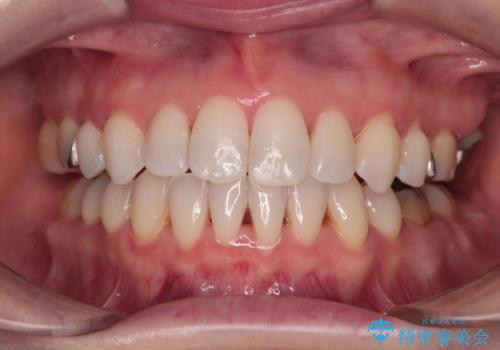

- 前歯のデコボコを治したいとのことで来院された患者様です。

上下顎ともに歯列全体の後方移動とIPR(歯と歯の間を削る)によってデコボコが解消するように設計し、インビザラインにより治療を行うこととしました。

上下ともにIPRを積極的に行っているため、舌の突出癖をしっかりと改善できないと、後戻りにより隙間やデコボコが早い段階で発現することになるため、舌のトレーニングが非常に大切になります。